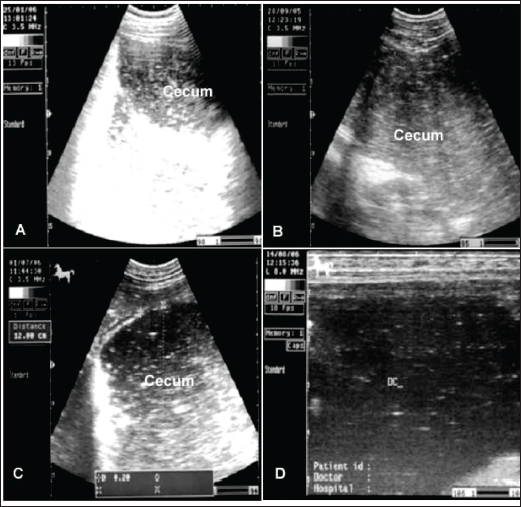

Fig. 6. Ultrasonogram of the cecum, left ventral colon (LVC), and right ventral colon (RVC) in 4 horses with flatulent colic. In A, the cecal wall appears echogenic in the absence of sacculations. In B, the LVC shows an echogenic wall with no sacculations. In C, the RVC shows a thin wall that appears echogenic in the absence of sacculations. In D, RVC appears in the absence of sacculations and with increased wall thickness. These organs contain a large amount of gas, which hinders their visualization.

Equines admitted with impaction colic are depressed and usually take the posture of dorsal recumbency. Generally, intestinal impaction is detected on rectal examination. Horses suffering from severe long-standing impaction may collapse when postmortem examination confirms the diagnosis (Teodoro et al., 2023). Generally, horses with impactive colic ultrasonographically show a large circular hyperechoic mass in the cecum that casts an acoustic shadow consistent with a dense material or enteroliths (Fig. 6). Sacculation is absent, and wall thickness may decrease or increase according to the presence of intestinal compromise. Similar findings were reported by Reef et al. (2004). The descending colon appeared severely distended with isoechoic ingesta and reduced motility, consistent with previous reports. In addition, the right dorsal colon is more echogenic and casts an acoustic shadow; the wall also appears more echogenic and thicker than in healthy animals. Diagnosis is made based on postmortem examination in cases that have not been recovered (Tharwat et al., 2008).